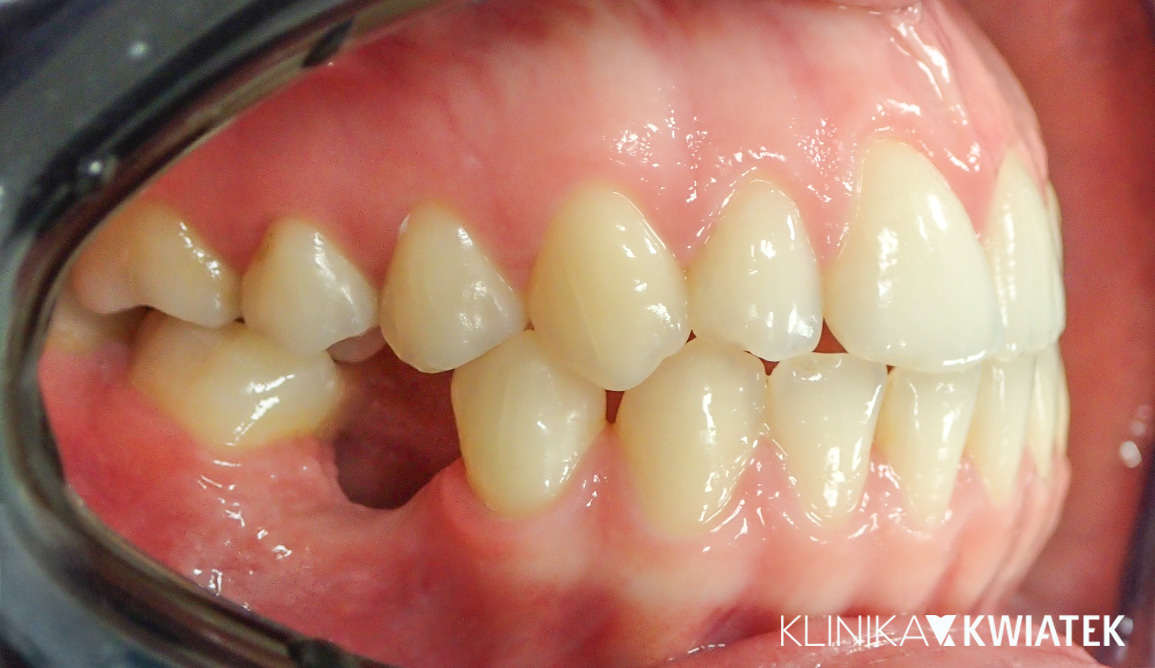

Najpierw zdrowie. Potem ortodoncja - stabilne warunki jamy ustnej jako fundament metamorfozy

Pacjent przez kilka lat pozostawał pod opieką kliniki, realizując etapowe leczenie zachowawcze i profilaktyczne, którego celem było pełne ustabilizowanie stanu jamy ustnej. Po zakończeniu leczenia próchnicy, ekstrakcjach zębów mądrości oraz zabiegach profilaktycznych – świadomie i w odpowiednim momencie – podjął decyzję o leczeniu ortodontycznym. Efektem kompleksowej terapii jest uśmiech będący zwieńczeniem lat świadomych decyzji, precyzyjnego planowania i konsekwentnego leczenia.